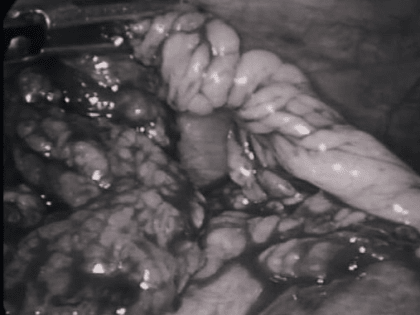

Нижегородские хирурги прооперировали ребенка с редчайшей патологией

Хирурги нижегородской областной детской клинической больницы прооперировали ребенка с редкой патологией.